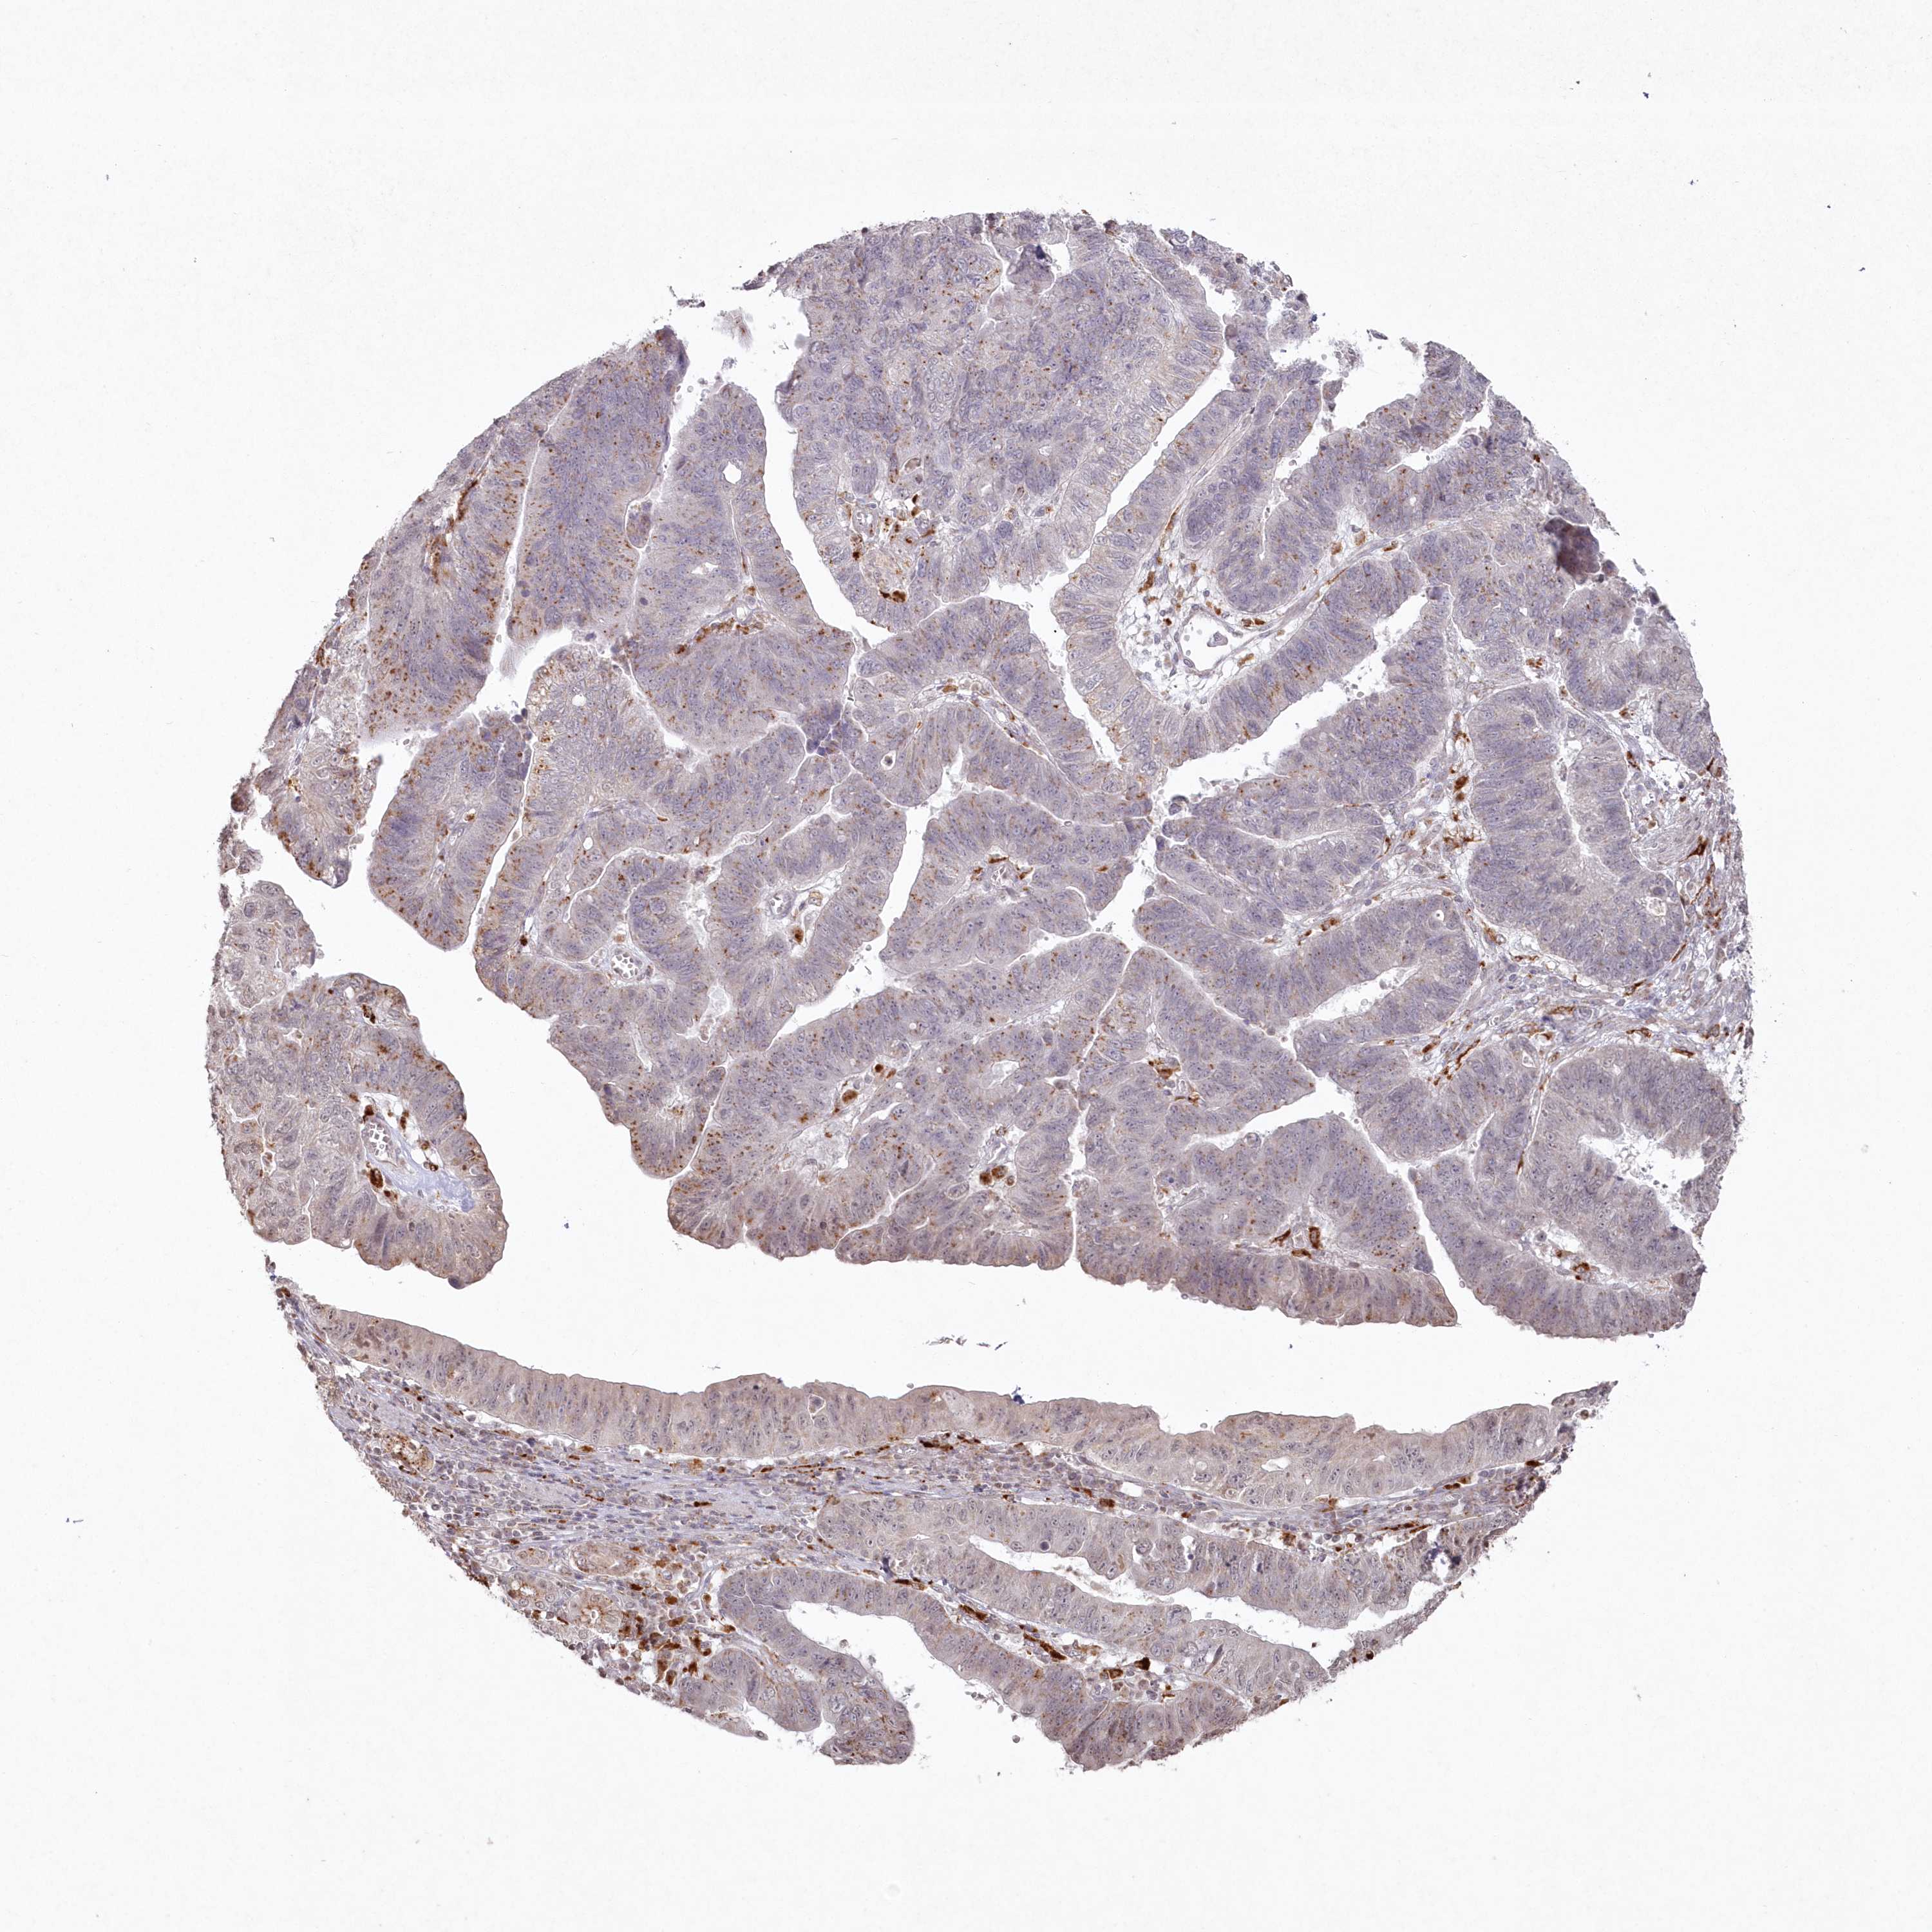

STOMACH CANCER - Protein expressioni

A mouse-over function shows sample information and annotation data. Click on an image to view it in a full screen mode. Samples can be filtered based on level of antibody staining by selecting one or several of the following categories: high, medium, low and not detected. The assay and annotation is described here.

Note that samples used for immunohistochemistry by the Human Protein Atlas do not correspond to samples in the TCGA dataset.

Antibody stainingi

Antibody staining in the annotated cell types in the current human tissue is reported as not detected, low, medium, or high, based on conventional immunohistochemistry profiling in selected tissues. This score is based on the combination of the staining intensity and fraction of stained cells.

Each image is clickable and will lead to virtual microscopy that enables deeper exploration of all samples and also displays staining intensity scores, fraction scores and subcellular localization as well as patient and tissue information for each sample.

Antibody HPA037770

Antibody HPA037771

Staining

High

Medium

Low

Not detected

Adenocarcinoma, NOS